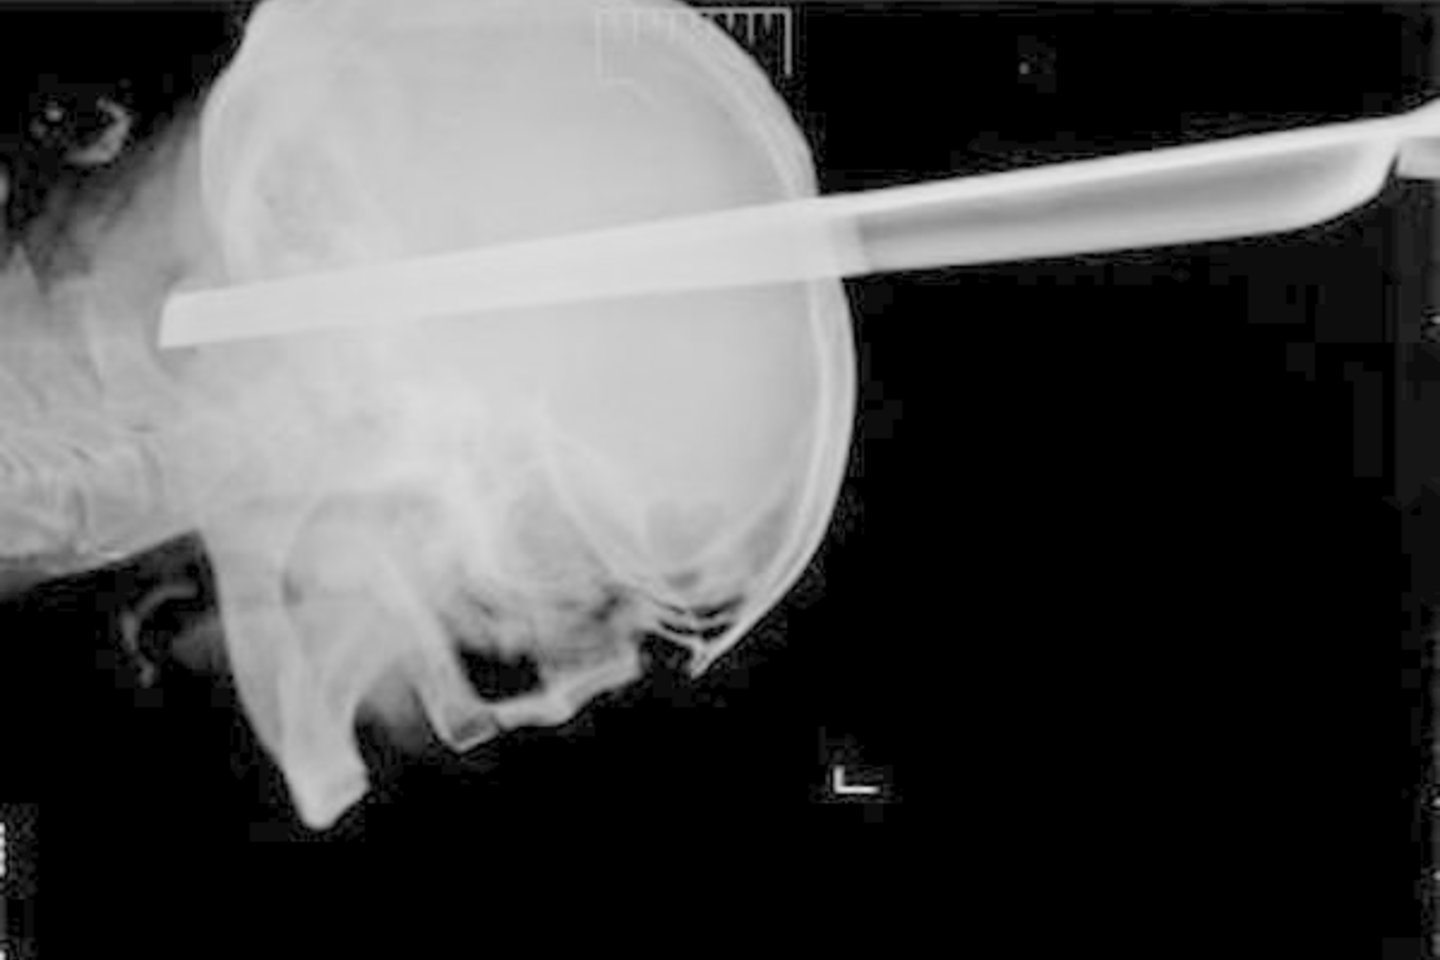

Vyras į ligoninės priimamąjį buvo atvežtas greitosios pagalbos automobiliu. Iš ten skubos tvarka nuvežtas į operacinę. Budinčių neurochirurgų brigada iš vyro galvos išėmė svetimkūnį. Pasak medikų, operacija praėjo be komplikacijų. Išėmę tokį didelį daiktą medikai tikėjosi gausaus kraujavimo, bet net jo nebuvo.